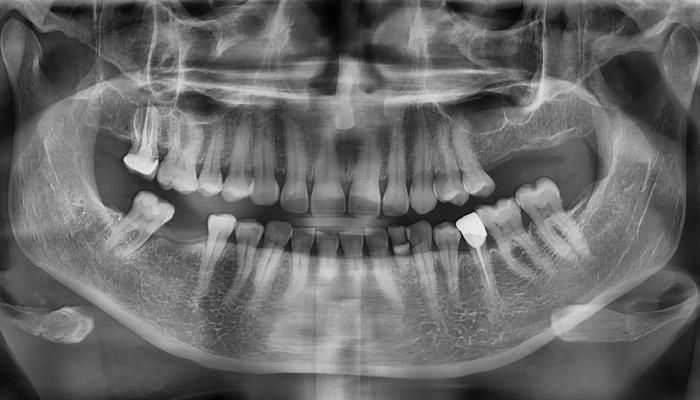

뼈이식 임플란트 전후 사례

• 식립 전

식립 후